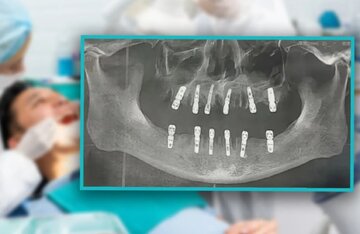

به گزارش خبرگزاری خبرآنلاین از سنندج، دکتر رستگار خسروی، رئیس دانشکده دندانپزشکی دانشگاه علوم پزشکی کردستان، در خصوص خطرات پوسیدگی دندان هشدار داد و اظهار کرد: حفره دهان بسیار حفره ای آلوده و پر از باکتری است که باکتریهای آن پس از مصرف مواد قندی، اسید تولید میکنند که این اسیدها به مرور زمان مینای دندان را از بین برده و باعث پوسیدگی دندان میشوند.

وی افزود: در مراحل اولیه، پوسیدگی دندان ممکن است با درد خفیفی همراه باشد که با مصرف مواد شیرین یا تغییر دما تشدید میشود. اما اگر این مشکل نادیده گرفته شود، پوسیدگی به بخشهای عمیقتر دندان نفوذ کرده و باعث درد شدید و مداوم میشود. در این مرحله، "درمان ریشه" تنها راه حل برای رفع مشکل است.

دکتر خسروی با تأکید بر اهمیت درمان زودهنگام پوسیدگی دندان گفت: اگر پوسیدگی دندان در مراحل اولیه درمان نشود، به تدریج به عصب دندان نفوذ کرده و باعث التهاب و عفونت آن میشود. در این مرحله، بیمار درد شدیدی را تجربه میکند که حتی با قطع محرک، درد نیز ادامه مییابد. در صورت عدم درمان به موقع، ممکن است عفونت به سایر قسمتهای دهان و حتی سایر نقاط بدن گسترش یابد.